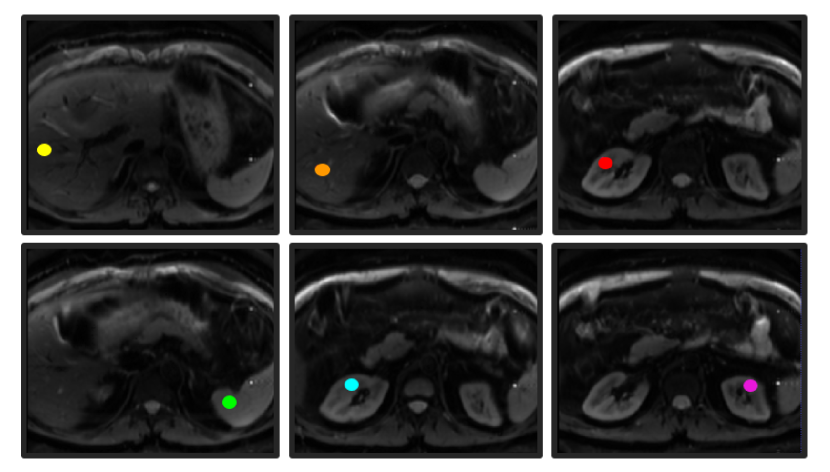

We assessed the added-value of SUPER-IVIM-DC in estimating the IVIM model parameter values from limited DWI data in a clinical setting. We first acquire high-quality DWI data of a human volunteer with 22 b-values: (0, 12.5, 25, 37.5, 50, 62.5, 75, 87.5, 100, 112.5, 125, 150, 175, 200, 225, 250, 375, 500, 625, 750, 875, 1000) sec/mm2 using a multi-slice single shot echo planar imaging (EPI) sequence with 6 directions. We calculated trace-weighted images from the different directions at each b-value using geometric averaging. We annotated 6 different regions of interest in the kidneys, liver and spleen selected from different slices. (Fig. 1).

Refer to caption

Figure 1: Abdominal ROI from different slices